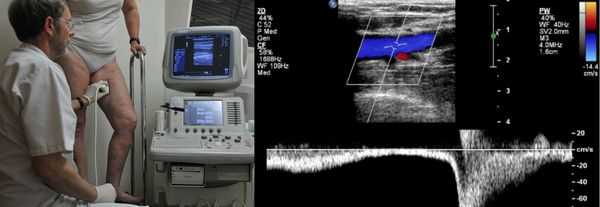

Диагностика хронической венозной недостаточности

Проведение диагностики ХВН на ранних стадиях способствует ускорению лечения. При диагностике важно определить стадию заболевания. После общего клинического осмотра врач проводит дуплексное ангиосканирование вен нижних конечностей, чтобы определить тактику лечения. Дуплексное ангиосканирование поможет оценить состояние исследуемых сосудов, увидеть места их сужений или расширений, а также выявить тромбообразования.

Одним из самых доступных методов диагностики данного заболевания является УЗИ, главным преимуществом которого является многоразовость применения без рисков для здоровья, безболезненность, а также возможность выявить нарушения в текущей работе венозного аппарата. [3]

Для получения лучшего результата обследование рекомендуется проводить во второй половине дня. Поскольку именно после дневной нагрузки на ноги можно провести более точную оценку состояния клапанов, диаметра вен и степени поражённости стенок. На тактику лечения влияет наличие тромба в просвете вен, который приводит к нарушению тока крови и несёт наибольшую угрозу для жизни пациента.